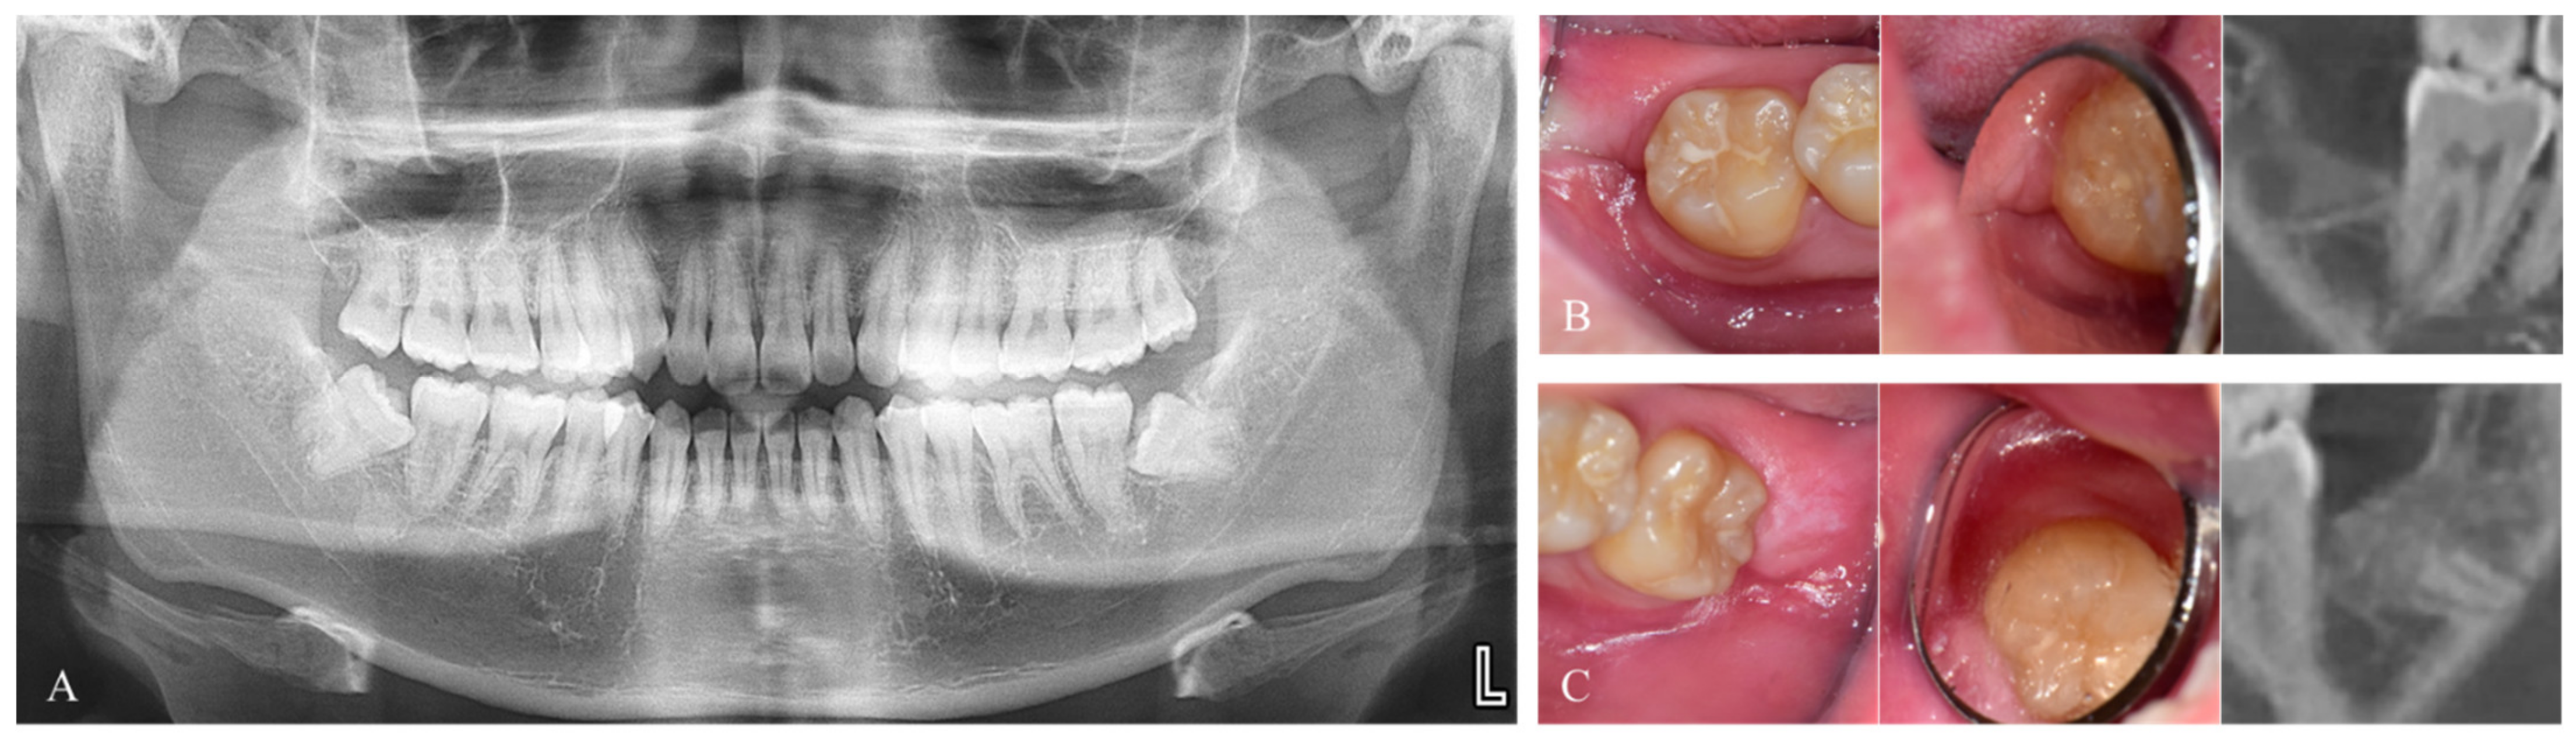

Figure 3.

Measurement of bony defect at the distal aspect of the adjacent second molar. (A–C). Immediate graft. (D,E). Delayed graft. (A,D). Pre-operative. (B,E). Post-operative. (C,F). Post-operative intraoral images.

Four patients (39.3 ± 6.3 years) did not undergo Auto-DDM grafting and were classified as the control group, while the other 16 (42.6 ± 13.3 years) received grafts. (Figure 4)

Pre-operative and post-operative images. (A). Pre-operative radiograph of a patient who had immediate graft on the left side with Auto-DDM, fabricated from the right mandibular third molar without any graft after the extraction on the right side. (B). Post-operative images at four months after the extraction without graft (Control group). (C). Post-operative images at three months. after the graft (Graft group).

Complications such as infections or graft failure did not occur. Although the pre-operative defects observed in the control patients (2.98 ± 1.77 mm) were smaller than those in the patients receiving grafts (10.02 ± 3.22), post-operative defects were similar in both groups (2.12 ± 0.59 and 2.29 ± 1.67 mm after 5.5 ± 2.6 and 4.6 ± 2.0 months, respectively, Table 2).

The improvement ratio was significantly higher in the graft than in the control group (77.9 ± 15.3 and 22.7 ± 26.2%, p = 0.001, Table 2). The pre- vs. post-operative change in defects was not statistically significant in control patients (p = 0.285), but a significant effect was observed in the graft group (p = 0.001, Figure 5).